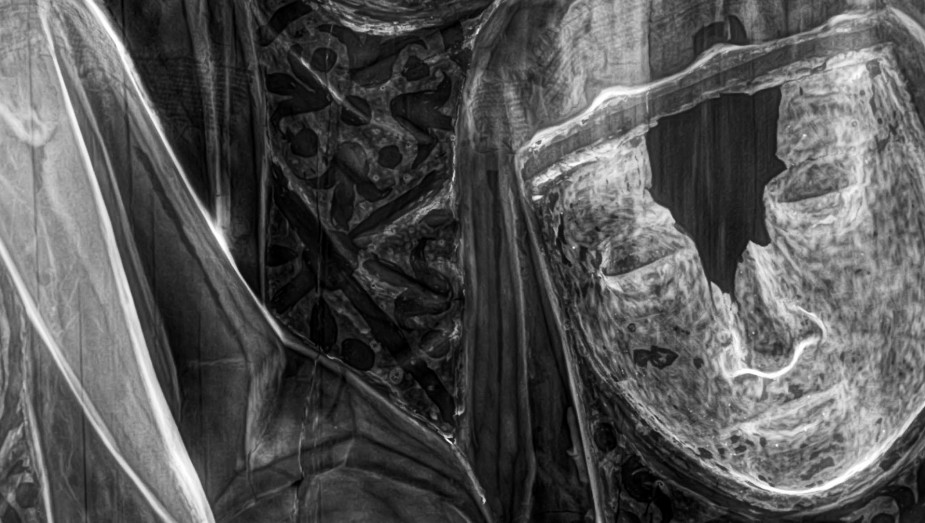

Radiología Digital como Herramienta Complementaria en el Dictamen de Bienes Muebles

Desde el descubrimiento de los rayos “X” y las placas radiográficas por Wilhelm Conrad Roentgen y su posterior difusión a través de la Asociación Físico médica de Wurzburg el 28 de diciembre de 1895, que fue la primera asociación que habló de los nuevos rayos que podían penetrar el cuerpo y fotografiar los huesos, ha habido muchos cambios tanto en la forma de obtener, procesar e incluso en la forma de visualizar, manejar y almacenar las placas radiográficas.